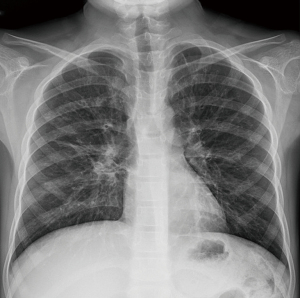

Initial laboratory findings, including complete blood count, liver function tests, CRP, amylase, and lipase, were unremarkable with a normal eosinophil count (4.3%, 450/µL). Fecal immunochemical testing was positive, and the fecal calprotectin (FC) level was 673 mg/kg. No pathogens were detected in stool culture or by multiplex polymerase chain reaction (PCR) (Seegene Inc.). Water’s view radiography demonstrated right frontal and bilateral maxillary sinusitis (Figure 1). Plain chest radiography demonstrated suspicious bronchiectatic lesions in both lung fields (Figure 2). Chest computed tomography (CT) demonstrated subsegmental atelectasis in the right middle lung field and diffuse bronchiectasis in both lungs (Figure 3). Abdominal CT and magnetic resonance (MR) enterography showed diffuse wall thickening from the distal ileum to the ascending colon. Pancreatic atrophy with diffuse calcification was observed with peripancreatic fat infiltration indicated chronic inflammation (Figure 4).